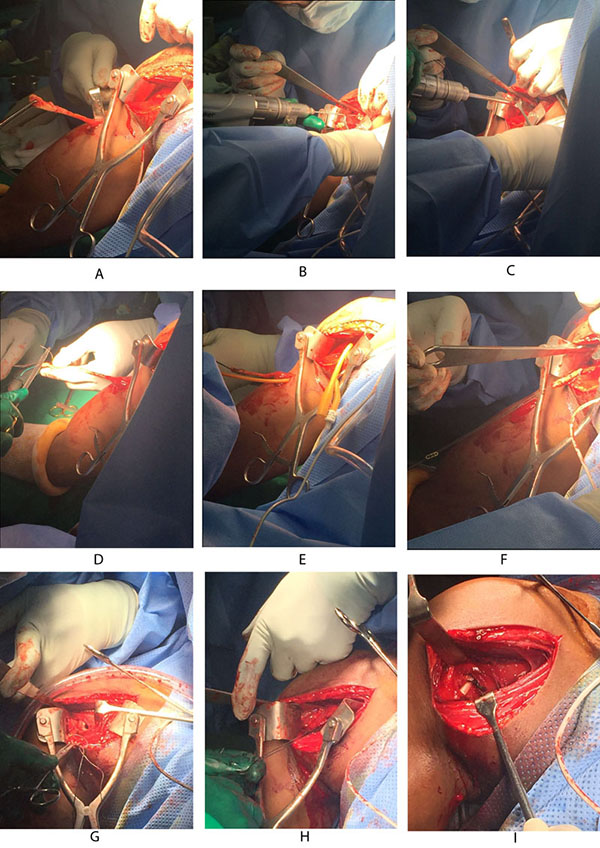

If the proximal end of biceps tendon could not be traced with this approach, then we need to make another 3cm incision in the subpectoral region, centered over the inferior border of the pectoralis major tendon. Superficial soft tissue is dissected to expose the fascia over the inferior border of the pectoralis major muscle. The fascia is incised from the lower border of the pectoralis muscle distally along the coracobrachialis and biceps muscles. The longitudinal, white tendon of the biceps tendon is identified and pulled out of the incision (Fig. 3A).

At this stage, we go back to our first incision site to prepare the tenodesis site. The distal part of the bicipital groove (DBG) is identified and cleared off soft tissues. A 2.7mmx 15” guide wire is drilled at an angle of 45º through the center of DBG. Care should be taken to avoid skydiving off the edge of the humeral shaft (Fig. 3B). The guide wire should be stopped as soon as the pin penetrates the posterior cortex (Fig. 4A). This is followed by drilling the anterior cortex over the guide wire with a calibrated cannulated drill, the size of which is the same as the measured diameter of the tendon (in our case, a 7-mm drill for a 7-mm tendon) (Figs. 3C, 4B). Care is taken to only drill up to the posterior cortex without engaging the cortex or plunging through. Depth of this bone tunnel is measured with the aid of a calibrated drill (TD- Tunnel Depth). Usually it is around a 20-25mm tunnel in adults. The hole should be lined up at the base of the biceps groove and cleared of soft tissue. Finally, the posterior cortex is drilled through with a 4.5-mm drill to allow for the passage of the cortical button (Fig. 4C).

A number-5 synthetic polyester suture (Ethibond Excel, Ethicon Inc; Johnson and Johnson, USA) is woven into the proximal biceps tendon using the Krackow technique or whipstitch suture technique (Fig. 3D). The tendon end to the DBG is retrieved again using the smallest size Foleys catheter (Fig. 3E). We used a 4-holed Endo Button without continuous loop (4.0 mm × 12 mm Endo-Button CL Ultra, Smith and Nephew, Andover, MA, USA). One limb of suture from the tendon end was threaded through the central two holes of the Endo Button (inside out – outside in). The other suture end from the tendon was passed through the terminal two holes of the Endo Button in a reverse manner i.e. from outside in – inside out (Figs. 4D, 7, 3F). It is important to make certain that the suture limbs are not tangled.

The Endo Button is loaded onto the Button deployment device and passed through bone tunnel (Figs. 4E, 3G). Once the button clears the posterior cortex, the deployment instrument can be removed while the button deploys itself, locking into place on the posterior cortex. Pulling on the sutures shuttles the LHB tendon into the humerus. The sutures are tensioned until the tendon is in contact with the posterior cortex (Fig. 3H). Finally, we advocate using a free needle to pass one suture through the tendon and tie down to the second suture to reinforce the fixation (Figs. 4F, 3I).

Unlike the use of the Biceps Button in the elbow, an additional interference screw is not required to achieve adequate fixation of the tendon. Rather, an additional suture is passed through the tendon of the LHB once it is shuttled through the humerus. This provides additional fixation strength to withstand physiologic loads. At this stage, cut the stay suture applied at superior border of pectoralis major tendon to complete the procedure. Intra-operative radiograph are taken to confirm the position of Endo Button. Wound wash is given and closed in layers. Cuff and collar is applied to support the arm for the first two weeks. Postoperative radiographs were obtained to assess the tenodesis location (Fig. 8A).